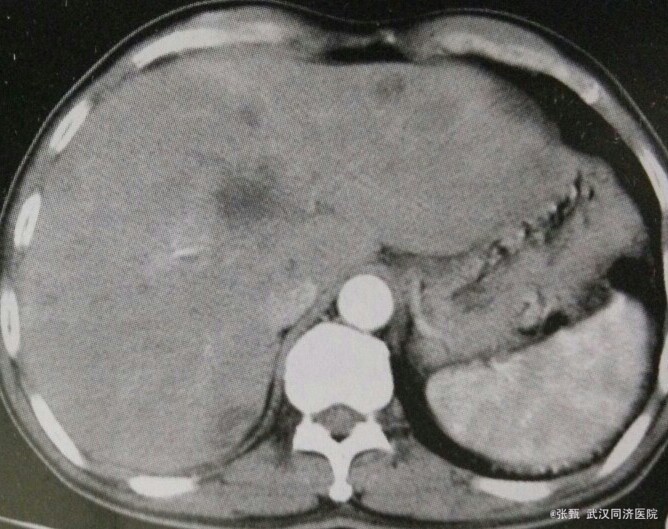

患者,男,60岁。 主诉:乙状结肠癌术后一年半,消瘦,纳差半年

查体:肝大,压痛 辅检:甲胎蛋白正常,CT示全肝广泛性不均匀低密度影,灶内见更低密度影,扫描动脉期肿瘤不规则强化,境界清楚,中央密度低,静脉期和实质期病灶强化消退呈现”牛眼征。“

诊断乙状结肠癌术后肝转移 建议行全身PET扫描,拒绝,行保守治疗